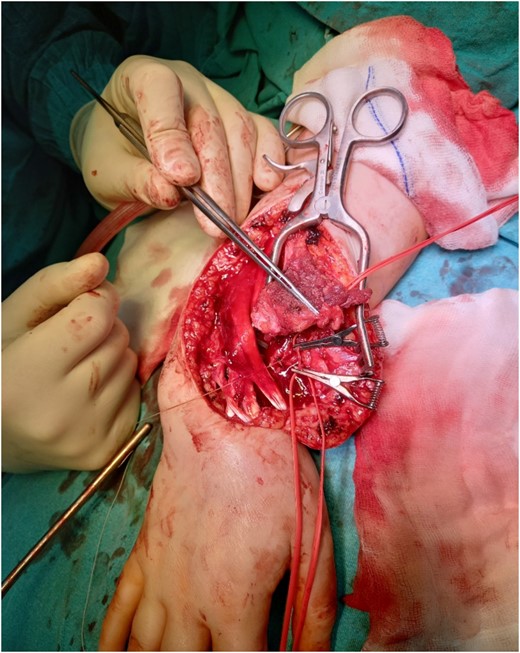

Resection of the tumor and harvesting of the bone graft from the ipsilateral proximal fibula was done simultaneously. We harvested a graft with a length of 8 cm with an inferior lateral geniculate branch and peroneal vessels to be used in the reconstruction of the defect that remained after the resection of the tumor (Fig. 2). After placing the graft in the place of the defect, the inferior lateral geniculate branch was anastomosed through a terminal-lateral anastomosis with the radial artery, while the vein was connected to the cephalic vein through an end-to-end anastomosis. The graft was fixed with a plate and screws, and two Kirschner wires (Fig. 3).

Reconstruction of the defect after resection of the GCTB of the distal radius and anastomosis of the vessels.